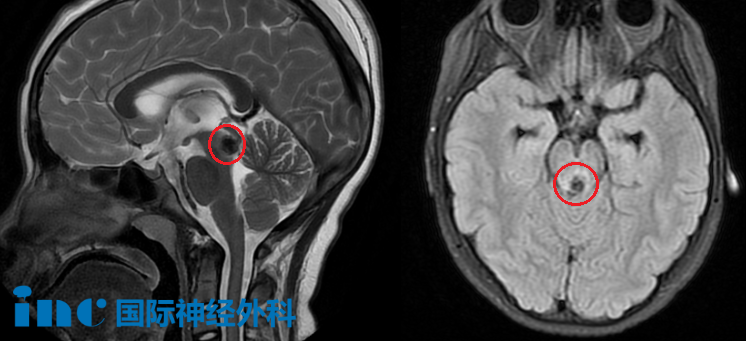

“我不能让孩子生活在恐惧之中,终日笼罩在未知出血风险的阴影下。”当获悉11岁女儿被诊断为脑干海绵状血管瘤时,湘湘内心充满坚定信念。无人能够预料,这颗深藏于脑干的海绵状血管瘤,竟会因出血压迫中脑导水管进而引发梗阻性脑积水。

原来,湘湘的海绵状血管瘤病灶位于中脑被盖区——这一区域在解剖学上属于极为特殊的“关键通道”。肿瘤一旦发生出血,极易直接堵塞大脑的“脑脊液循环管道”,导致脑脊液循环通路中断,从而引发急剧的颅内压力升高,若未能得到及时处理,甚至可能进展为脑疝,直接危及患者生命。